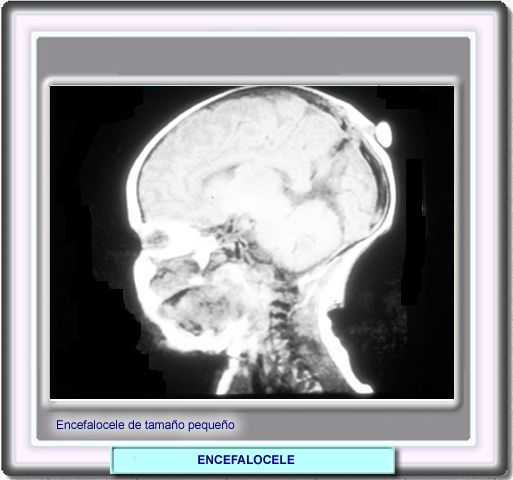

El diagnóstico del encefalocele es evidente, excepto cuando se trata de una lesión de tamaño pequeño que, adicionalmente, puede estar cubierta de piel y cabellos.